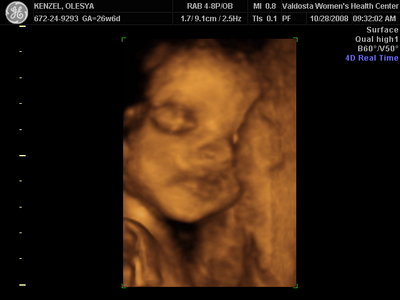

Еще одна Джианнка:

| Вложения: |

KENZEL,OLESYA_5.JPG [ 60.02 КБ | Просмотров: 1511 ]

Катюш, какой прикольный бутузик ! Олесь, после фотки средней - точно прям похожи!